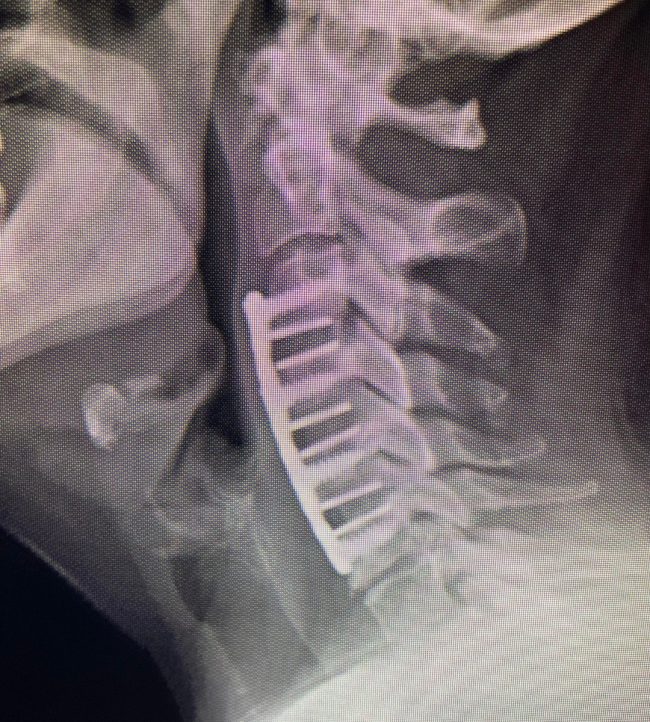

Combined Anterior–Posterior Repair Restores Function After C5 Diving Fracture

As a Neurosurgeon, spinal fractures of the neck from diving accidents are things that I see way too often. This young man dove from a boat into shallow water. He presented with some numbness in his arm and hand. He had a fracture with the instability of his cervical spine at C5, requiring anterior and…